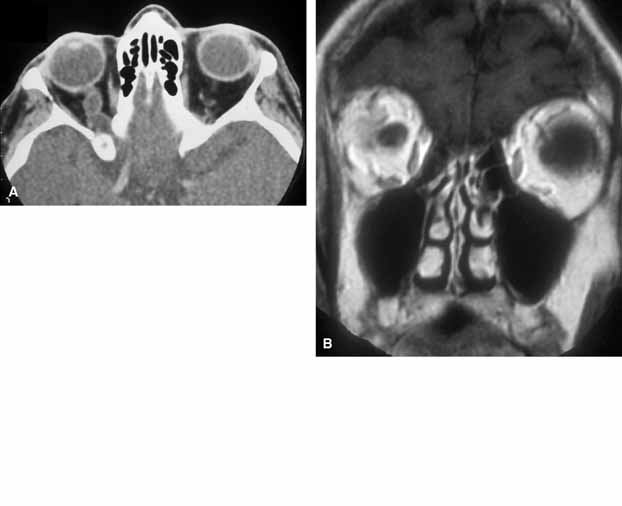

Because of the variable presentation of dermoid cysts, Shields et al.,5 have suggested a classification of orbital dermoid cysts by their association (or lack of association) with suture lines of the skull and assist the clinician in appropriate management. Cysts are classified as juxtasutural, sutural, or soft-tissue dermoid cysts. Those cysts adjacent to the bony suture line but not firmly attached are juxtasutural. A sutural dermoid cyst is firmly attached to bony sutures causing bone erosion, tunnels or an hourglass configuration. Soft tissue dermoid cysts may be strictly confined to soft tissues without any connection to a bone structure. Intradiploic epidermoid cysts are distinctly uncommon and were not included in Shields' classification (Fig. 3).

Fig. 3 In a coronal image of a computed tomogram, an intradiploic dermoid cyst is shown to involve the superior orbital rim and roof of the left orbit displacing the globe downward (A). The intraoperative cavity (B) of the cyst is observed with the evacuated keratin debris shown (C).